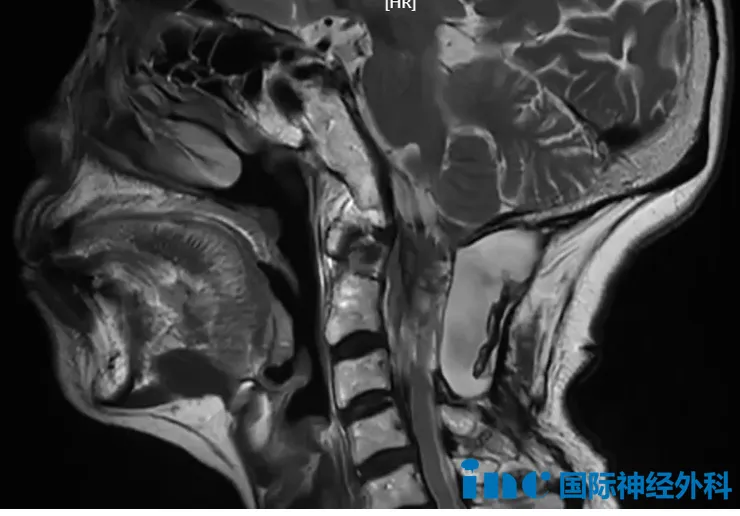

这位年过七旬的陈女士,颈椎C1—C2脊膜瘤出现复发,因突发晕厥、伴有记忆障碍就诊。此前已历经两次手术,此番复发后,她反复出现头晕、四肢无力(蹲起困难)、四肢麻木、行走不稳,多次摔倒,右腿时常伴有刺痛和灼烧感,严重干扰日常生活;晕倒期间更造成了肋骨和左臂骨折。医生评估后认为有手术指征,但风险较高。

巴特朗菲教授给出评估:"第三次手术,可能仍无法实现完全切除,因为必须把保护神经功能放在首位;但在这一前提下,我们仍会尽力清除更多肿瘤。"而陈女士对此早已想得通透:"教授,咱们的想法是一致的。我七十多岁了,要是能让我再好好活个二十年,就已经非常、非常满足了。"在这一刻,对生命质量与长度的追求,在医患之间的彼此信任中,悄然找到了平衡。